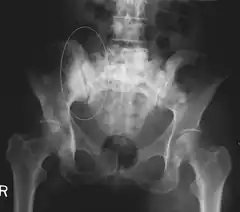

Skeletal Radiography

A plain film x-ray of the entire body can identify bone metastasis. However, the sclerotic or osteolytic lesions must be at least 1 cm in diameter.[14] A combination of X-ray, CT and MRI scans may be most sensitive in the diagnosis of cancerous bone metastasis.[14]